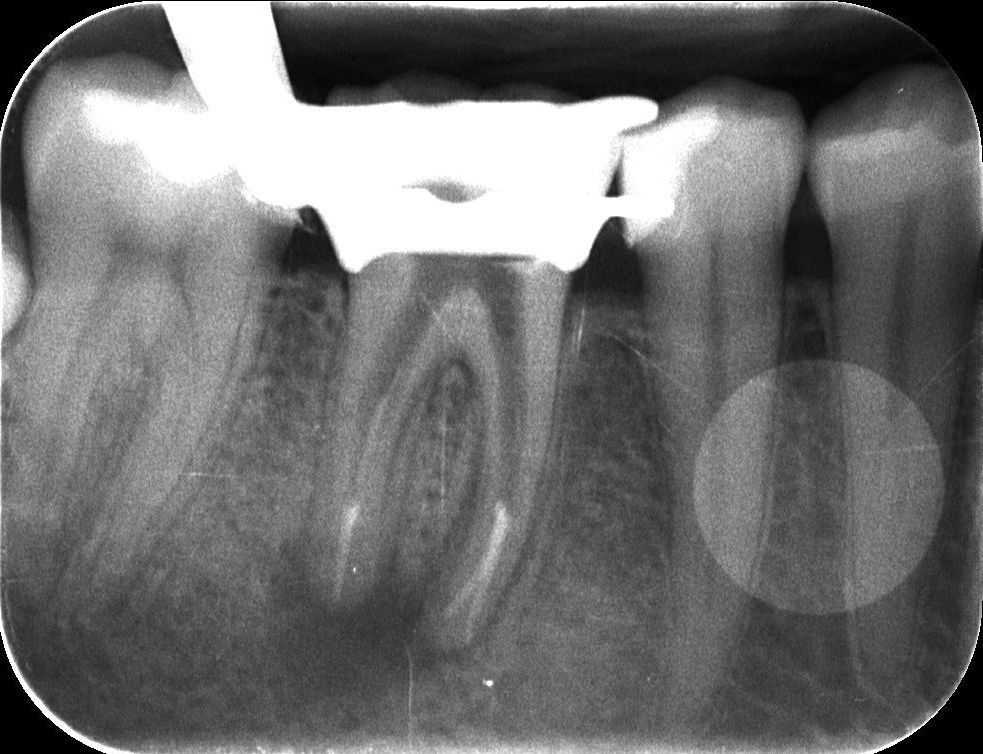

Az alábbi felvételen látható a kész gyökértömés első szakasza, amikor a gyökértömés alsó harmadát készítjük el meleg guttapercha-technikával. A kiindulási röntgenfelvétellel összehasonlítva látható, hogy a gyökértömő anyaggal szépen sikerült elérni a gyökércsúcsok végéig.

mikroszkópos gyökérkezelés 3. kép